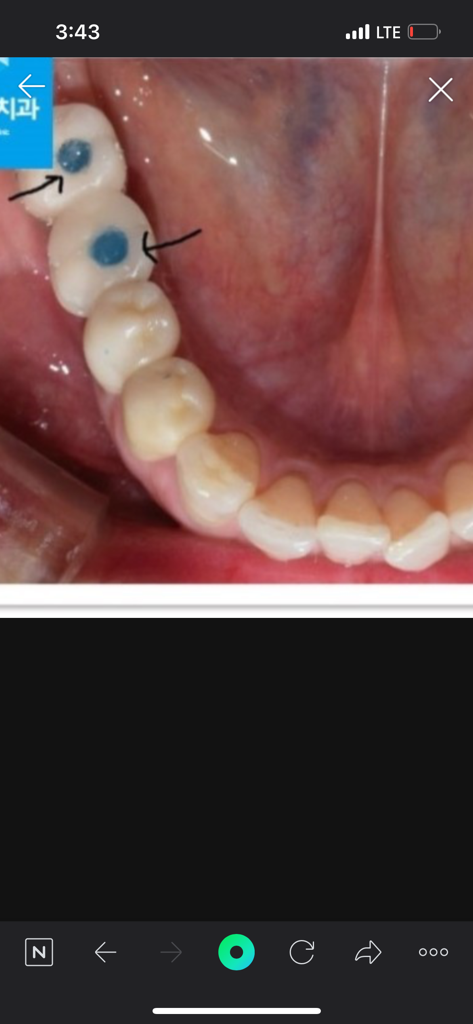

임플란트 마무리 모양이 어떤가요?

원래 이빨 생김새의 모양으로 마무리하지않나요?

저는 어금니를 임플란트 했는데요...

제사진은 아니고

저런식으로 마무리로 끝낫는데 (디테일은 제꺼가 더 이상함;; )

현재 파란색인 부분은 아마 레진 등을 통해서 수정할 것으로 보입니다. 다만 이는 오히려 시멘트 타입보다 유지 관리가 좋습니다. 해당 공간의 hole을 통해서 임플란트 머리와 뿌리 부분을 분리할 수 있는데, 추후 임플란트 머리가 부서지거나 문제가 생기더라도 위쪽 보철물만 교체할 수 있어 장점이 있습니다.

해당 임플란트는 단순히 시멘트 타입보다 훨씬 어려우며 이렇게 해주신 것은 치과의사 선생님이 환자를 위해 임플란트를 오래 쓸 수 있게 구조적으로 만들어주신 것입니다.

임플란트 뿌리와 머리를 연결하는 나사 구멍을 일부러 만들어서 차후에 수리를 수월하게 하게 하기도 합니다.

보청 치아색으로 메구게 되면 심미적으로 신경이 쓰이지 않지만 나사에 접근을 쉽게 하기 위해서 치아색과 다른 색의 치과재료로 충전을 하는경우도 있습니다.

scrp형태의 임플란트로서 홀부분을 치아색이 나는 레진으로 채워넣을 경우 제거할 때 어려움이 있어 사진상으로 보이는 것처럼 티나는 색상을 넣기도 합니다. 많이 신경쓰이시면 치아색으로 바꾸실 수 있습니다.

치아 형태로 보철물이 제작됩니다. 임플란트 가운에데이 잇는구멍은 임플란트 보철물과 안에잇는 구조물을 연결시키는데 필요한 나사가 들어가는공간으로 그 부분은 일반적으로 치아색 나는 재료로 채주고 마무리를 하게 됩니다.

치아가운데 원형의 홈을 통해 나사를 조였다 뺐다 해서 임플란트 위 크라운을 제거할수 있게 제작 합니다.